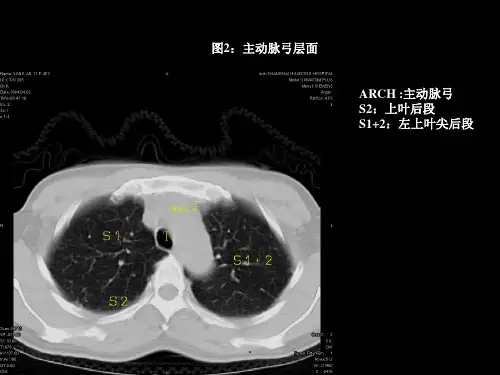

(三)肺(lung)。